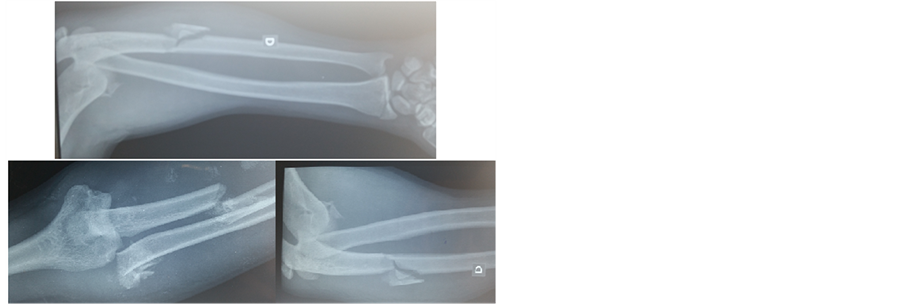

This is a male, 35 year-old patient, builder, without any remarkable medical history who fell from a high place and applied an excessive load to his wrists, which were in extension. He had deformity of both wrists, severe pain and functional disability. Associated to severe pain and functional disability of the right elbow. The initial physical exam found a “dinner fork” deformity in both wrists, increased temperature, severe pain and functional disability. Deformity of the right elbow with ecchymosis. Antero-posterior and lateral wrist X-rays of the wrists and right elbow were taken, which showed dorsal radiocarpal dislocation and fracture of the radial and ulnar styloid process in both wrists (Figure 1 and Figure 2). Dislocation of the right elbow with complex fracture of the radial head and ulnar shaft of the same right upper limb (Figure 3).

Figure 3. Right elbow before treatment.